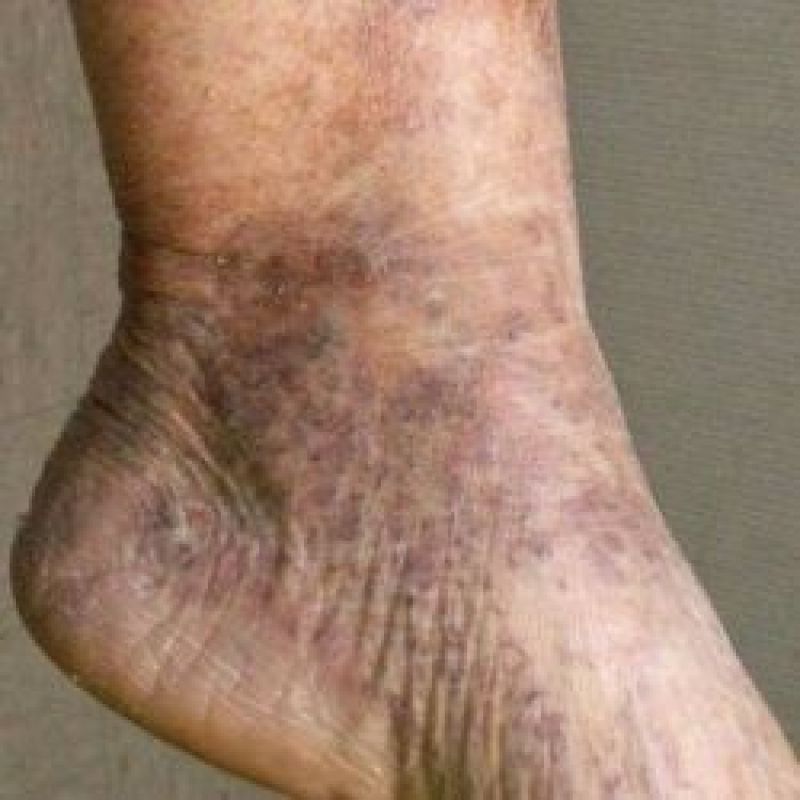

ਲੱਤਾਂ ਜਾਂ ਚਮੜੀ ਦਾ ਨੀਲਾ ਜਾਂ ਜਾਮਣੀ ਹੋਣਾ: ਤੁਸੀਂ ਸ਼ਾਇਦ ਵੇਖਿਆ ਹੋਵੇਗਾ ਜਦੋਂ ਬਹੁਤ ਠੰਢ ਹੁੰਦੀ ਹੈ, ਤਾਂ ਤੁਹਾਡੀ ਚਮੜੀ ਨੀਲੀ ਹੋ ਜਾਂਦੀ ਹੈ ਪਰ ਕਈ ਵਾਰ ਅਜਿਹਾ ਵੀ ਹੁੰਦਾ ਹੈ ਕਿ ਗਰਮੀਆਂ ਵਿਚ ਵੀ ਤੁਹਾਡੀਆਂ ਉਂਗਲਾਂ ਦਾ ਰੰਗ ਨੀਲਾ ਹੋ ਜਾਵੇ। ਅਜਿਹੀ ਸਥਿਤੀ ਵਿਚ 'ਬਲੂ ਟੋ ਸਿੰਡਰੋਮ' ਹੋ ਸਕਦੀ ਹੈ, ਜਿਸ ਵਿਚ ਤੁਹਾਡੀਆਂ ਖ਼ੂਨ ਦੀਆਂ ਨਾੜੀਆਂ 'ਚ ਰੁਕਾਵਟ ਪੈਦਾ ਹੋ ਜਾਂਦੀ ਹਨ।

ਸੱਟਾਂ ਦੇ ਨਿਸ਼ਾਨ: ਕਈ ਵਾਰ ਸਾਡੀਆਂ ਲੱਤਾਂ 'ਤੇ ਸੱਟਾਂ ਜਾਂ ਜਲਣ ਦੇ ਨਿਸ਼ਾਨ ਰਹਿ ਜਾਂਦੇ ਹਨ, ਜੋ ਕਿ ਲੰਬੇ ਸਮੇਂ ਤਕ ਸਹੀ ਨਹੀਂ ਹੁੰਦੇ। ਅਜਿਹੀ ਸਥਿਤੀ ਵਿਚ ਲਿਵਰ ਦੀ ਸਮੱਸਿਆ, ਜਾਂ ਕੋਈ ਅੰਦਰੂਨੀ ਸਮੱਸਿਆ ਹੋ ਸਕਦੀ ਹੈ। ਲੱਤਾਂ 'ਤੇ ਲਾਲ ਨਿਸ਼ਾਨ ਹੋਣਾ: ਚਮੜੀ 'ਤੇ ਧੱਫੜ ਹੋਣਾ ਆਮ ਮਰੀਜ਼ਾਂ ਦੀ ਸ਼ਿਕਾਇਤ ਹੁੰਦੀ ਹੈ। ਇਹ ਨਿਸ਼ਾਨ ਲਾਲ, ਗੂੜ੍ਹੇ ਲਾਲ, ਜਾਂ ਜਾਮਣੀ ਹੋ ਸਕਦੇ ਹਨ।

ਕੁੱਝ ਮਾਮਲਿਆਂ ਵਿਚ ਇਨ੍ਹਾਂ 'ਤੇ ਖਾਰਸ਼ ਵੀ ਹੋ ਸਕਦੀ ਹੈ। ਇਸ ਲਈ ਇਹ ਸਿਰਫ਼ ਐਲਰਜੀ ਵਾਲੀ ਪ੍ਰਤੀਕ੍ਰਿਆ ਹੋ ਸਕਦੀ ਹੈ। ਹੋਰ ਮਾਮਲਿਆਂ ਵਿਚ ਇਹ ਕਿਸੇ ਗੰਭੀਰ ਬਿਮਾਰੀ ਦੇ ਲੱਛਣ ਹੋ ਸਕਦੇ ਹਨ। ਅਜਿਹੀ ਸਥਿਤੀ ਵਿਚ ਖ਼ੂਨ ਦੀ ਸਮੱਸਿਆ ਜਾਂ ਗਠੀਏ ਦੀ ਸਮੱਸਿਆ ਹੋ ਸਕਦੀ ਹੈ।